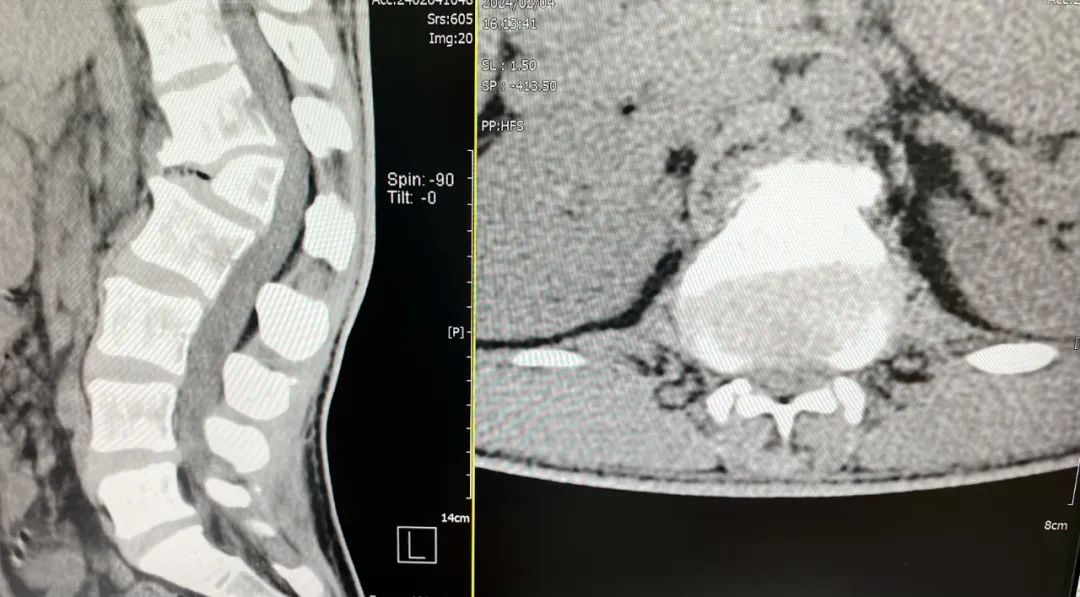

▲CT平扫示:腰1椎体半椎体畸形继发椎管狭窄